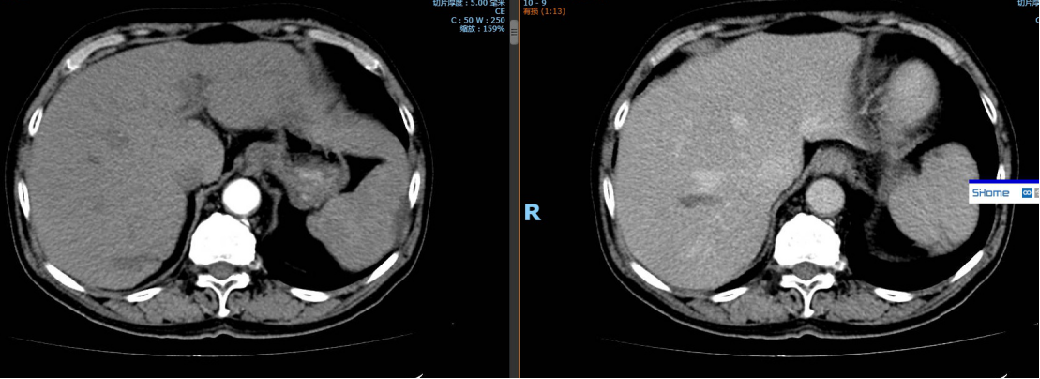

影像学检查:

CT:肝S5肝细胞癌,大小约55×68×55mm,有假包膜,另胆囊结石

动脉期:

静脉期:

冠状面: